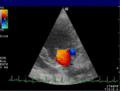

Bei der farbkodierten Doppler-Sonografie wird für einen großen Bereich eines konventionellen Ultraschallbildes (Color-Window) die örtliche Doppler-Frequenz (= mittlere Flussgeschwindigkeit) und deren Schwankungsbreite bestimmt. Damit möchte man die Turbulenz der Strömung abschätzen. Aufgrund der statistischen Bewegungen der Streuteilchen ist die Schwankungsbreite der Fließgeschwindigkeit jedoch stets größer als die Turbulenz. Das Ergebnis wird in Falschfarben auf dem B-Bild überlagert, also in Farbtönen von rot und blau für verschiedene Blutgeschwindigkeit und grün für Turbulenz. Hierbei steht üblicherweise die Farbe Rot für Bewegung auf den Schallkopf zu, während mit blauen Farbtönen Flüsse weg von der Sonde codiert werden. Bereiche der Geschwindigkeit 0 werden durch die Elektronik unterdrückt.

-

Anwendung des Doppler-Verfahrens bei einer Herzuntersuchung: Mitralklappeninsuffizienz -

Farb-Doppler und PW-Doppler. Innerhalb der Stenose ist wegen der hohen Flussgeschwindigkeit und des resultierenden Alias-Effekts die Geschwindigkeit in Blau kodiert. -